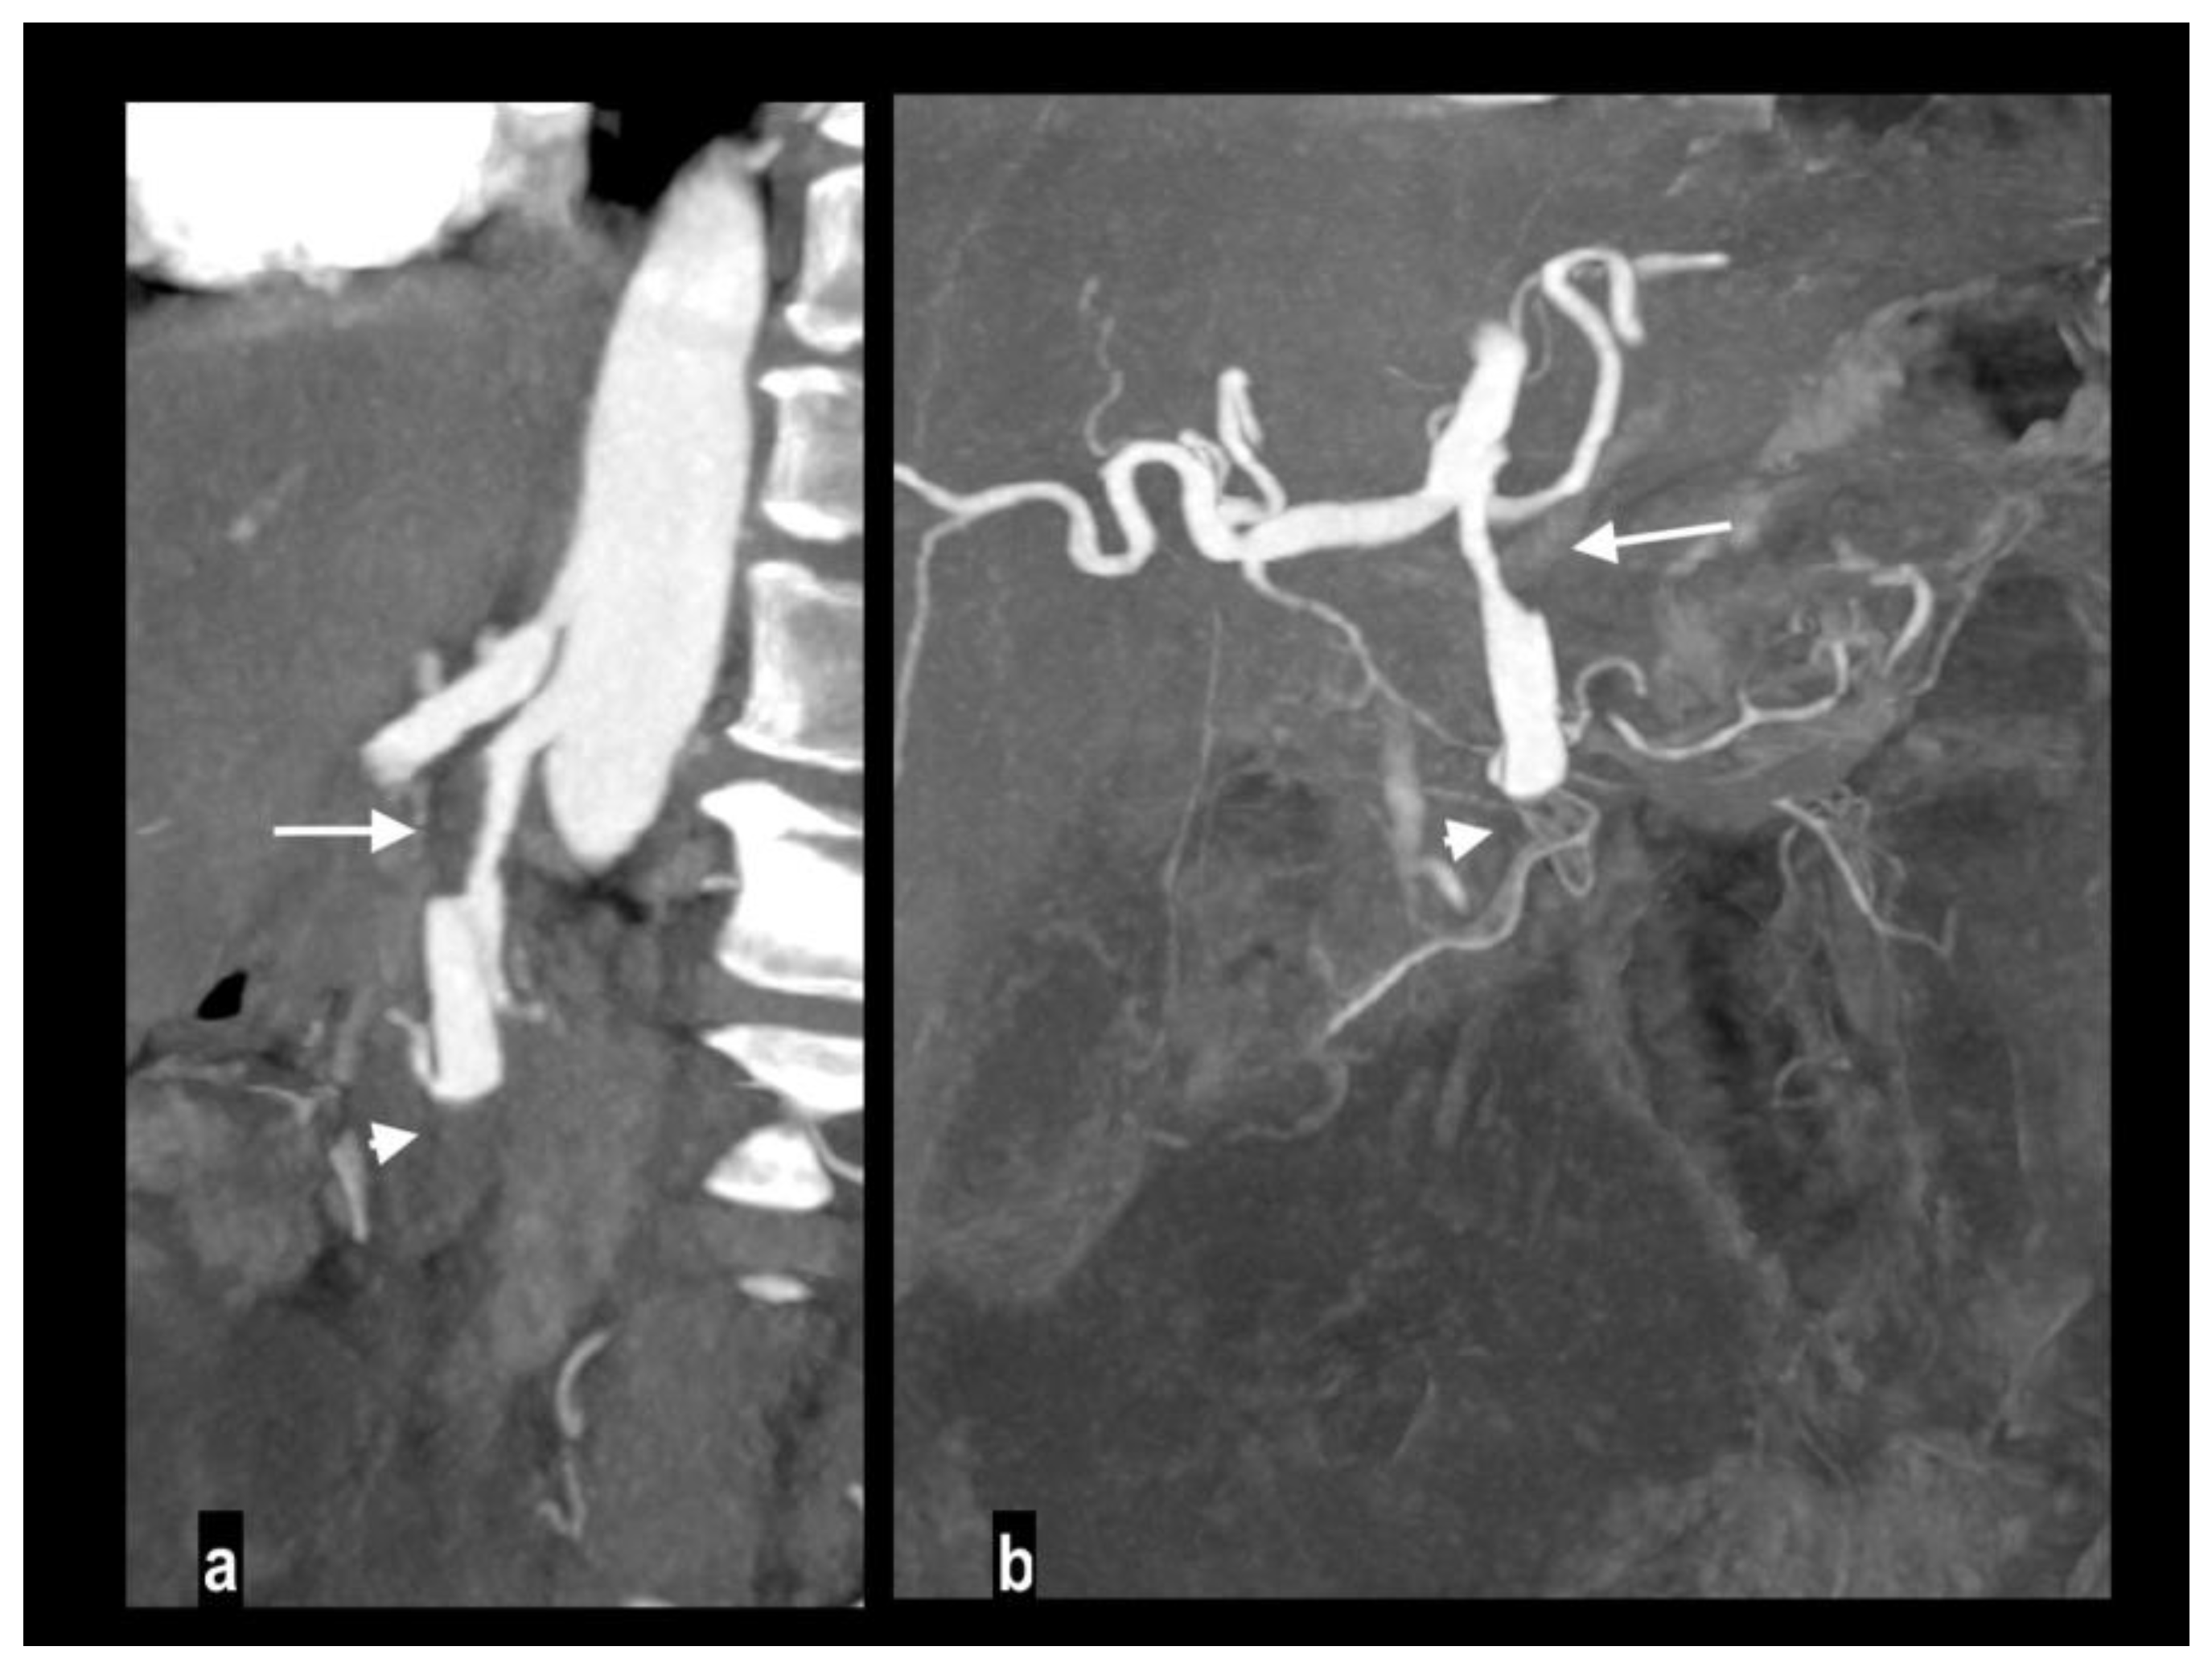

Figure 3. Acute abdominal pain in a 52-year-old with atrial fibrillation. Oblique sagittal and coronal MIP arterial images showed embolic occlusion of the middle SMA, with subtle peripheral segmentary enhancement of distal lumen by a collateral vessel (figure 3a-b). Hypoenhancing ileal and right colon walls were well appreciated in comparison to jejunal loops on left abdominal side (figure 3c). A left renal infarct is also present (figure 3d). Patient underwent a right colectomy.